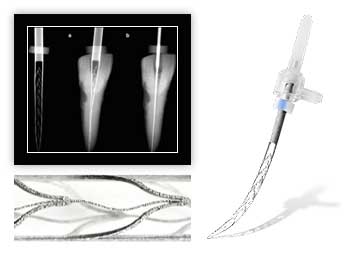

Наше оборудование